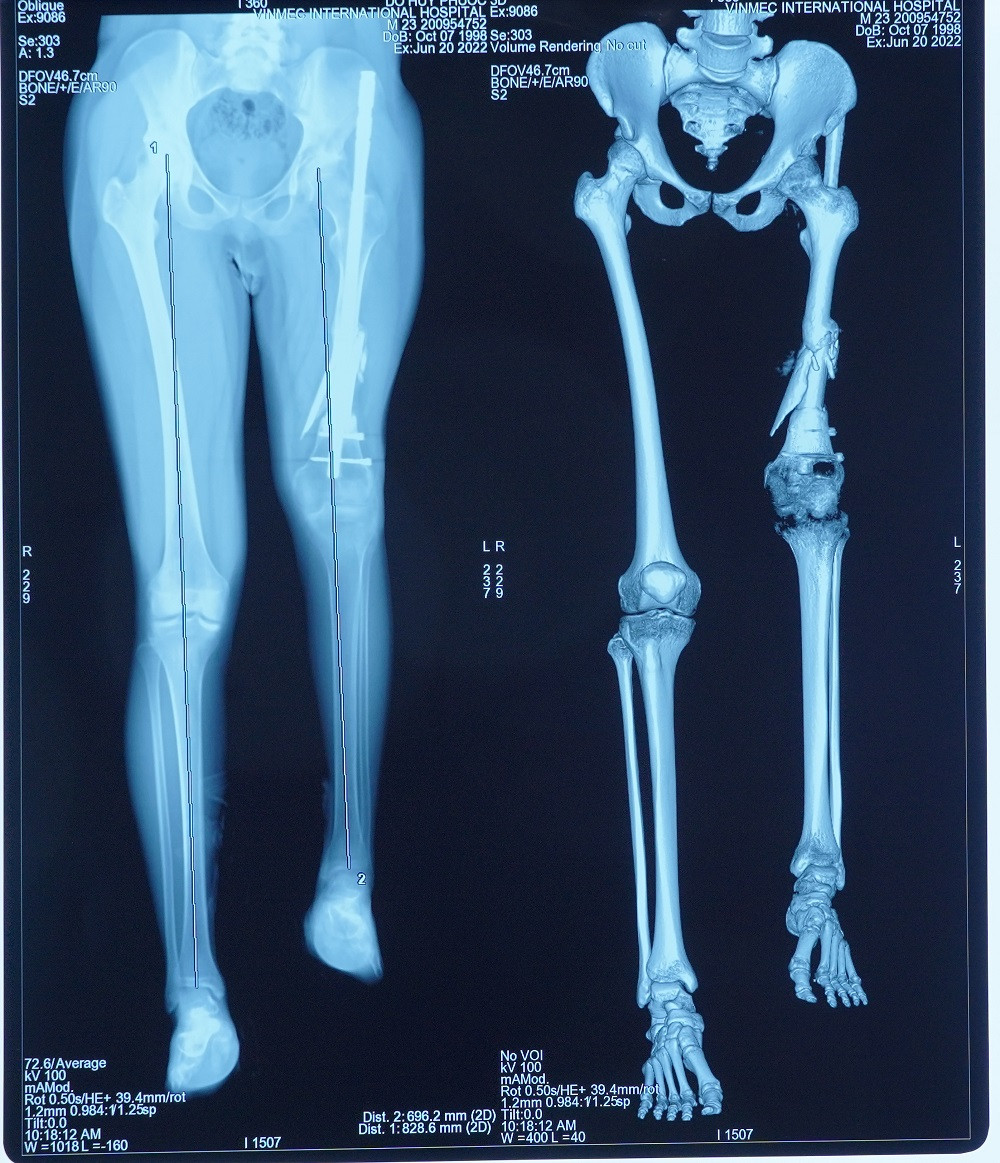

Các bệnh nhân kéo dài chân thông thường (kéo cả 2 chân) sẽ được kết hợp kéo cả 2 xương trên và dưới đầu gối là xương đùi và xương chày. Trường hợp của anh P. nan giải hơn khi chỉ kéo dài một chân trái. Cái khó là làm sao để tránh tình trạng 2 đầu gối bên cao bên thấp. Vấn đề cần khắc phục chính là ở xương đùi ngắn và phần mềm tại đây co rút. Điều trị đúng nguyên nhân rất quan trọng và cũng là thách thức khi kéo dài một khoảng cách lớn ở riêng phần đùi.

Sau nhiều lần thăm khám, hội chẩn, GS. Trần Trung Dũng và ekip đã đi đến phác đồ điều trị 2 giai đoạn: Gỡ dính và kéo phần cơ đang co rút ra tối đa có thể, sau đó thực hiện phẫu thuật ghép xương đùi và đầu gối nhân tạo bằng vật liệu y sinh. Toàn bộ kích thước, trọng lượng xương nhân tạo được tính toán bằng công nghệ 3D để đảm bảo gần với chân lành nhất. Bệnh nhân đã 24 tuổi và ổn định chiều cao nên không lo bị chênh lệch chi và tránh nguy cơ gãy xương lần nữa.